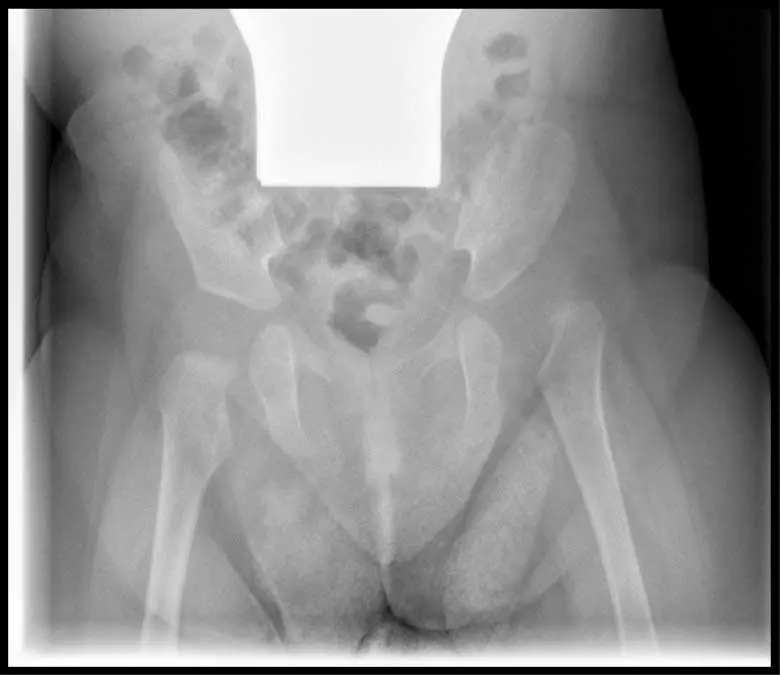

Diagnose von Hüftdysplasie

Hüftdysplasie kann bei der Untersuchung des Neugeborenen durch den Arzt festgestellt werden. Der Arzt wird den Hüftgelenken des Kindes besondere Aufmerksamkeit schenken. Er führt verschiedene Tests durch, um die Beweglichkeit der Hüften zu überprüfen.

Zusätzlich zu den körperlichen Untersuchungen können folgende bildgebende Verfahren eingesetzt werden:

- Röntgen: Ein Röntgenbild kann bei älteren Kindern oder wenn die Diagnose durch Ultraschall nicht eindeutig ist, eingesetzt werden.